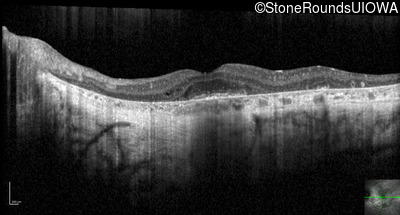

Optical Coherence Tomography - Right - 20/50 sc

Exemplar / OCT Stack